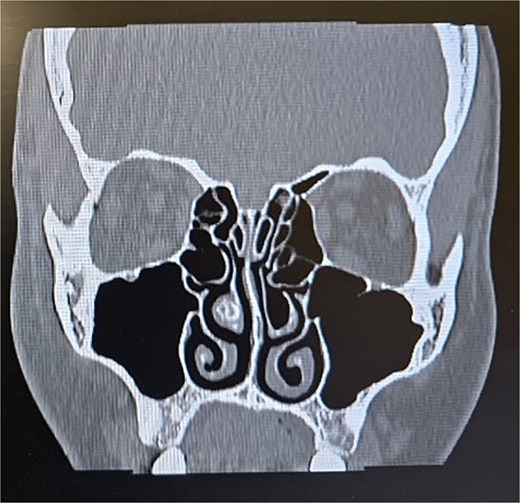

Clinical examination, including anterior rhinoscopy and nasal endoscopy, revealed a midline nasal septum and bilateral hypertrophy of the inferior and middle turbinates, with otherwise normal nasal mucosa. A CT scan of the paranasal sinuses in the coronal plane demonstrated bilateral pneumatization of the middle turbinates consistent with CB. Additionally, the right inferior turbinate was pneumatized, with communication to the ipsilateral maxillary sinus (Figs 1 and 2).

Paranasal sinus CT scan in the coronal plane showing bilateral concha bullosa in the superior turbinates and pneumatization of the right inferior turbinate (inferior concha bullosa).